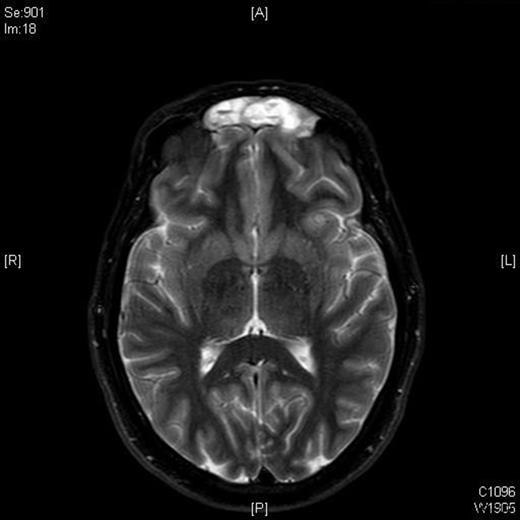

A follow-up MRI scan in 2009 showed contrast-enhancing soft tissue abnormalities within both of the frontal sinuses and the left ethmoid sinus (Figures 1 and 2). A CT scan showed soft tissue abnormalities in these locations (Figure 3). An incisional biopsy confirmed a subepithelial ameloblastoma.